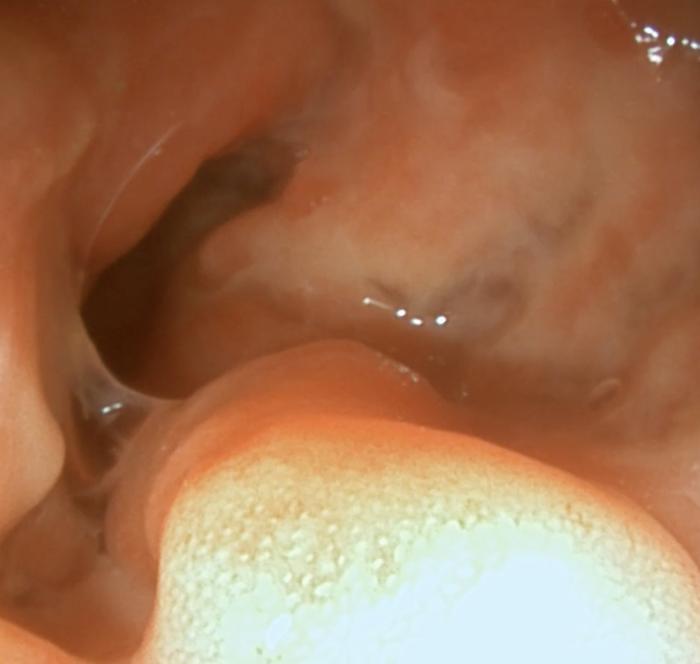

Dada la gravedad del cuadro clínico y los cambios ecográficos, se decidió realizar una endoscopia digestiva superior e inferior. A nivel macroscópico, el estómago presentaba eritema leve de forma difusa. La mucosa duodenal se observó eritematosa, friable y con dilatación de los conductos lacteales. La mucosa del colon se encontraba eritematosa, friable, granular, con sangrado al contacto y áreas nodulares marcadamente irregulares (Figura 4-5, Vídeo 1-2).